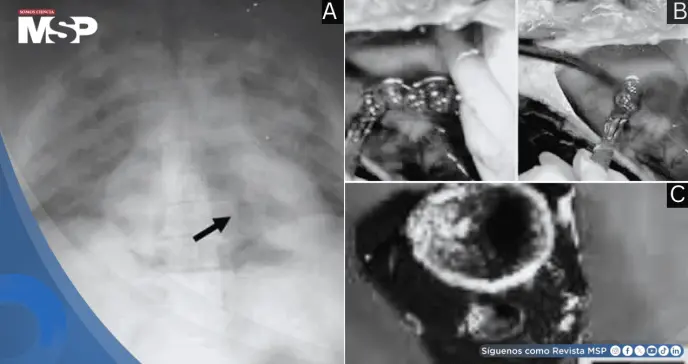

La radiografía previa a la autopsia mostró presencia masiva de gas en la circulación portal y en el ventrículo derecho.

Durante la disección cardíaca se documentó mediante video la emisión masiva de burbujas de gas al incidir la pared del ventrículo derecho, que se encontraba marcadamente distendido y flotaba anormalmente en el líquido pericárdico. El quiste hepático estaba vacío y presentaba signos evidentes de punción reciente.